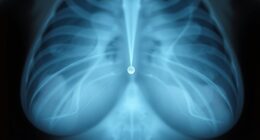

Brustimplantate und Krebs: Tumorerkennung trotz Implantaten

Das Vorhandensein von Brustimplantaten kann die Krebsentdeckung erschweren, aber fortschrittliche bildgebende Verfahren bieten vielversprechende Lösungen – erfahren Sie, wie man die Früherkennung von Tumoren verbessern kann.